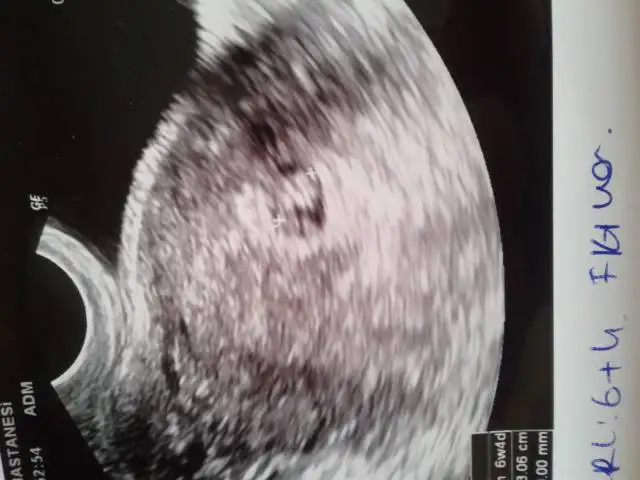

Tatli annişler bende kısmetse Kasım annesi olacağım bugün kesemi gördüm 5mm di ultrasona göre 5+2 günlük hamileyim fakat son adet tarihime göre hesapladigimda 5+4 oluyorum fakat doktorum bi sıkıntı olmadığını söyledi bakalım 10gün sonra tekrar kontrol by defa kalp atışlarıni duyacağım :))

merhaba kızlar dün öğlen lekelenmem olduğu için dr a gıttık bebeğimin kalp atışlarını gördüm duydum o heyecanla eve geldik akşam 18:30 gibi lekelenmem olduğunu gördüm 5 dk sonra kanama başladı oğlum olduğu için hemen gdemedim hastaneye eşimde 1.5 saatlık yola gitmişti annemi aradım geldi beraber gıttık ben kürtaj olurum düşüncesiyle içeri girdim muayene olurken oda neeeeee kuzum hala benimlee inanamadımm dr da şaşırdı çünkü kan geldi yani sonrası siyah kahverengi lekelerr sata göre 7+3 bebeğe göre 6+4 idik dun bugun 6+5 olduk ama kesemiz ufak o canımı sıktı riskli bir gebelik dedi iğne vurdular eve geldim ama suanda k. rengi ve siyah lekelenme hala devam ediyor kesemizin ufak olması canımı sıkıyor çünkü bebeğin alanı daralıyor kese büyümezse muhtemelen kuzumu kaybedicem ama dr bu şeklide başlayıp sağlıklı olan gebelikler var suanda bişey diyemem dedi buda kuzummm